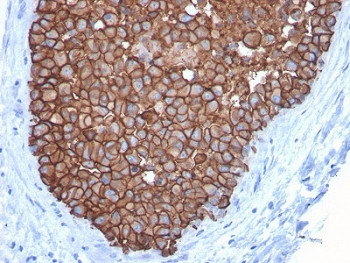

Product information "Anti-HER2 / ErbB2, clone ERBB2/3092"

0.2 mg/ml in 1X PBS with 0.1 mg/ml BSA (US sourced) and 0.05% sodium azide. Recognizes a protein of 185kDa, which is identified as c-erbB-2/HER-2/neu. Its epitope is localized in the extracellular domain. C-erbB-2/HER-2 is a member of the EGFR family. This mAb is specific and shows minimal cross-reaction with other members of the EGFR-family. Receptors of this family are located on the plasma membrane and consist of an extracellular ligand-binding domain that is connected to a large intracellular domain by a single transmembrane sequence. c-erbB-2/HER-2 protein is over-expressed in a variety of carcinomas especially those of breast and ovary. Protein function: Protein tyrosine kinase that is part of several cell surface receptor complexes, but that apparently needs a coreceptor for ligand binding. Essential component of a neuregulin-receptor complex, although neuregulins do not interact with it alone. GP30 is a potential ligand for this receptor. Regulates outgrowth and stabilization of peripheral microtubules (MTs). Upon ERBB2 activation, the MEMO1-RHOA-DIAPH1 signaling pathway elicits the phosphorylation and thus the inhibition of GSK3B at cell membrane. This prevents the phosphorylation of APC and CLASP2, allowing its association with the cell membrane. In turn, membrane-bound APC allows the localization of MACF1 to the cell membrane, which is required for microtubule capture and stabilization. [The UniProt Consortium]

| Application: | IHC (paraffin) |